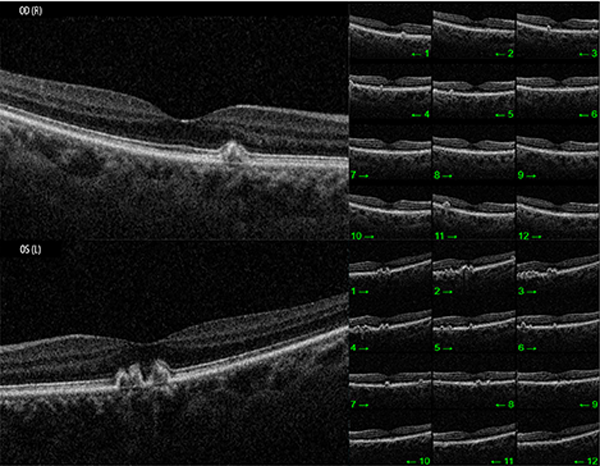

En el examen del fondo de ojos se observó una mácula de brillo conservado en AO y múltiples lesiones redondeadas de menos de un cuarto de diámetro papilar en polo posterior que comprometían a la mácula en OD, perifoveales en OI y en retina periférica 360° por fuera de las arcadas vasculares de AO, sin otros hallazgos relevantes (fig. 1).

Ante estos hallazgos se continuó la evaluación con OCT que evidenció un perfil anterior macular conservado y una alteración del perfil posterior compatible con depósitos drusenoides a nivel del EPR (fig. 2) con mínima acumulación de líquido a nivel sub-EPR.

Figura 1. Fundus OCT ojo izquierdo y derecho respectivamente.

Figura 2. OCT macular de ojos derecho e izquierdo.